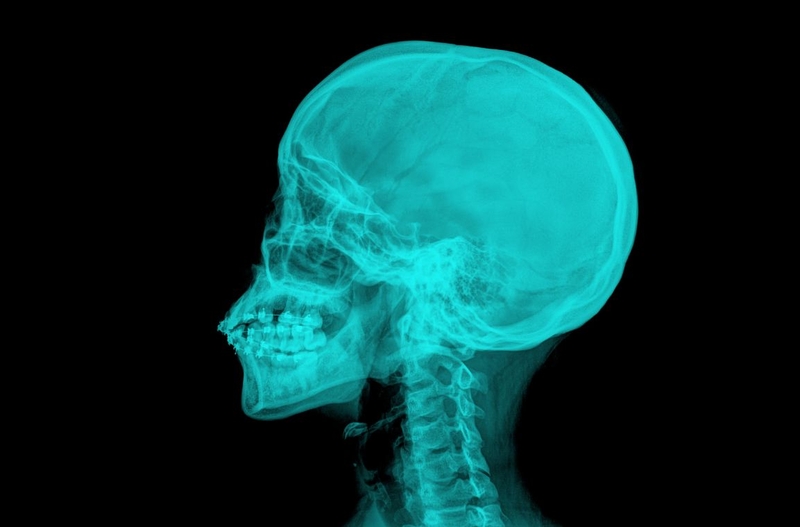

Chụp X quang tai mũi họng là kỹ thuật chẩn đoán hình ảnh được các bác sĩ chỉ định để đánh giá, chẩn đoán, theo dõi các bất thường hoặc các bệnh về tai mũi họng. Có nhiều kỹ thuật, tư thế chụp X quang vùng tai, mũi, họng khác nhau. Tùy từng trường hợp cụ thể, bác sĩ sẽ chỉ định bệnh nhân thực hiện kỹ thuật phù hợp.

Chụp X quang là kỹ thuật sử dụng bức xạ năng lượng cao để mô phỏng hình ảnh bên trong cơ thể. Trong quá trình thăm khám, chẩn đoán, theo dõi bệnh, các bác sĩ sẽ chỉ định phương pháp này để hỗ trợ quan sát các bất thường bên trong cơ thể mà mắt thường không thể nhìn thấy.

Chụp X quang ở tai, mũi, họng cũng giống như chụp X quang ở các bộ phận khác. Máy chụp X quang chiếu ra các tia X. Các tia X đi qua các cấu trúc xương, mô và khoang, hốc ở tai, mũi, họng rồi ghi lại thành hình ảnh trên phim X quang tai mũi họng với các màu sắc xám, trắng, đen với mức độ đậm nhạt khác nhau. Căn cứ vào hình ảnh của phim chụp, bác sĩ có thể phát hiện ra các bất thường ở tai - mũi - họng. Nếu kết quả chưa đủ căn cứ để kết luận chính xác, bác sĩ có thể chỉ định thêm các xét nghiệm khác.